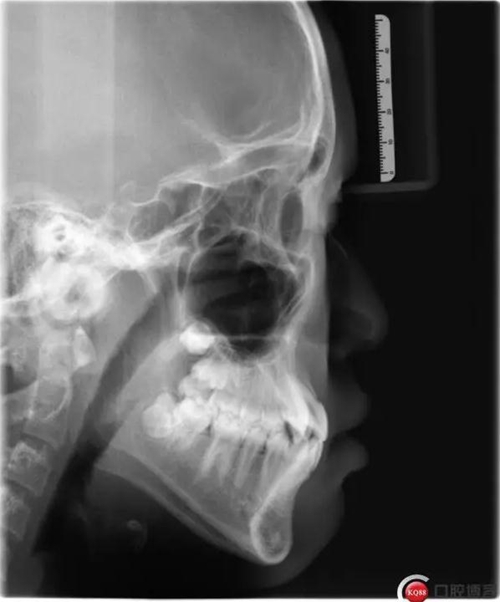

1500866161_694151.jpg1500866311_947305.jpg

此病例主要考慮的是垂直骨面型,矢狀骨面型,前牙覆合覆蓋及尖牙關(guān)系,側(cè)貌